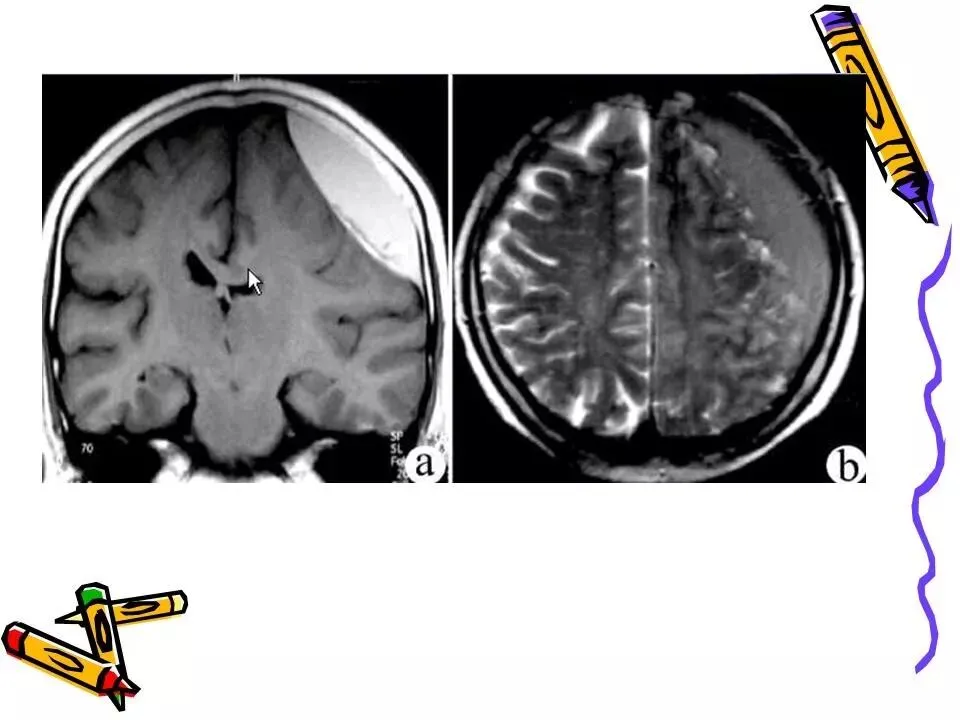

>常见颅脑外伤CT诊断(PPT)

常见颅脑外伤CT诊断(PPT)